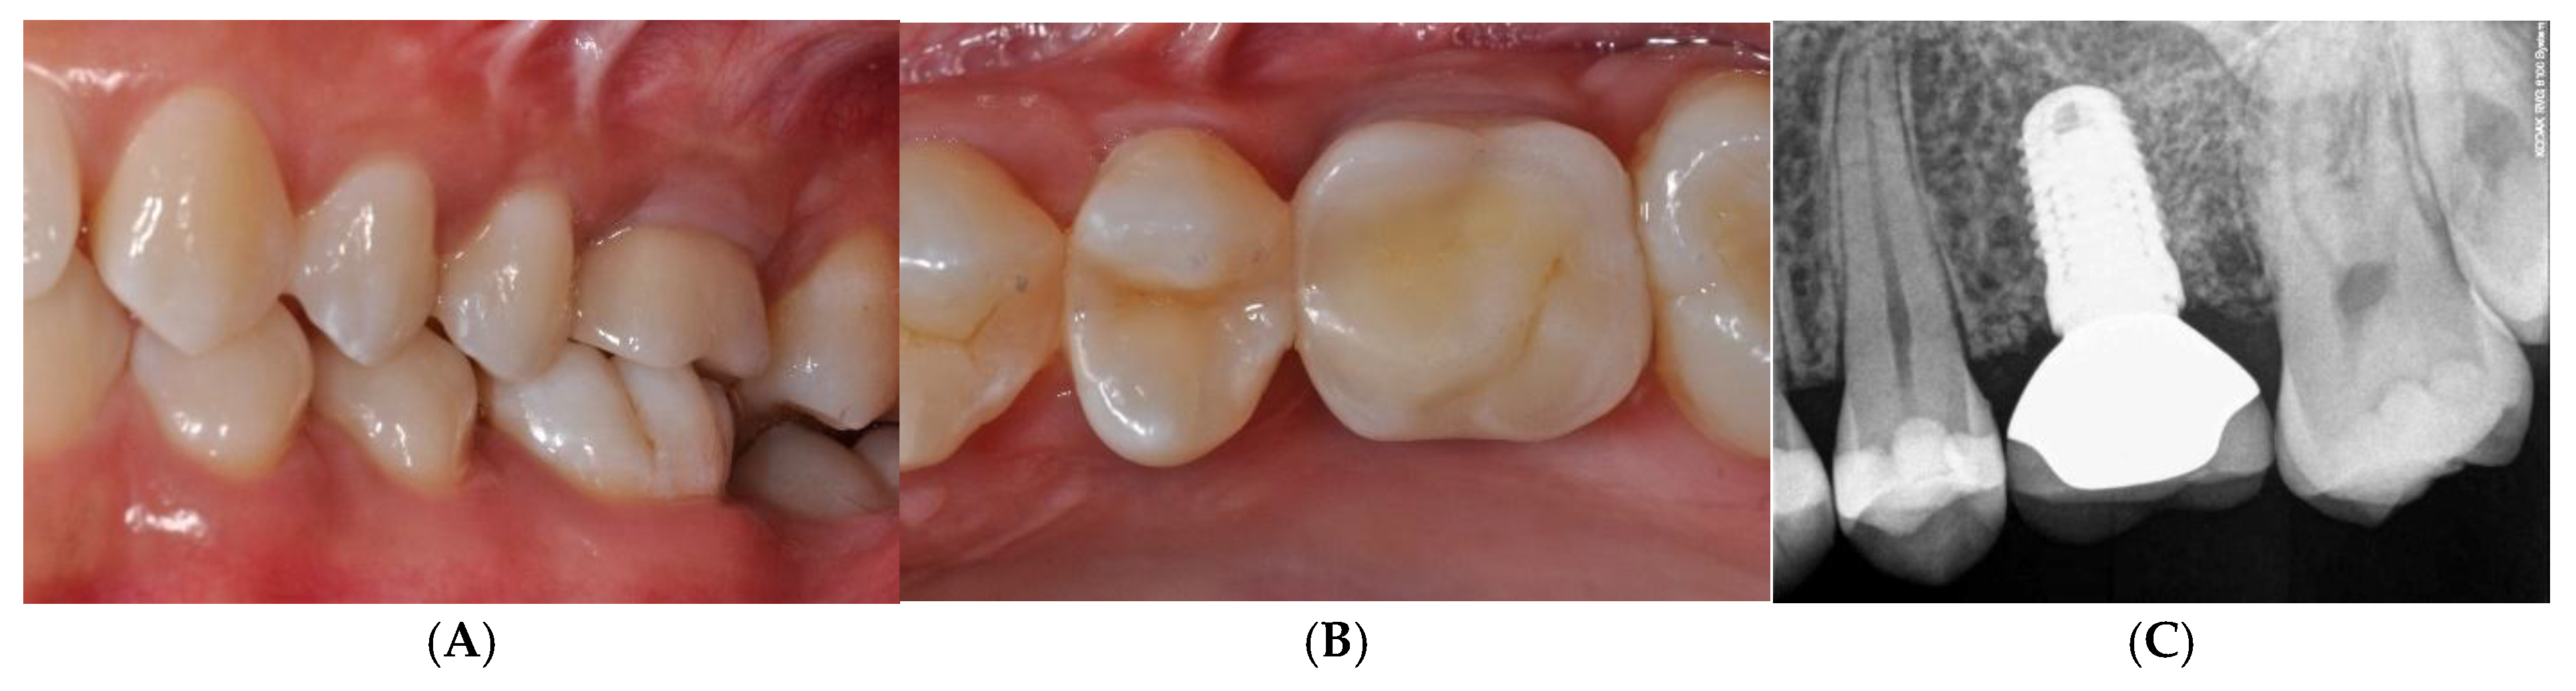

Figure 8.

Provisional restoration was applied for progressive loading. At 6 months after implant insertion, a definitive porcelain-fused-to-metal crown was cemented (A–C).

This GBR procedure was effective for the reconstruction of the horizontal defect, and the bone underneath the TR-dPTFE membrane appeared well mineralized after a healing period of 10 months. The implant was inserted in well-matured and vascularized bone and achieved primary stability very easily. No additional ridge augmentation was required for implant placement. Regenerated bone was found to be uniform across the defect and was hard and well integrated. The patient was very satisfied with the aesthetic result of the prosthetic rehabilitation and the improved masticatory function. She was monitored at least twice a year, when she returned for professional hygiene sessions. There were no problems of peri-implantitis, unscrewing of the implant abutment screw or soft tissue recession. The 5-year clinical and radiographic follow-up after functional prosthetic loading showed the augmented hard and soft tissues well maintained, with no marginal bone loss around the implant and a bone density within the limits (Figure 9A,B).

Figure 9.

5-year clinical (A) and radiographic (B) follow-up after functional prosthetic loading showed augmented hard and soft tissues, which were well maintained.